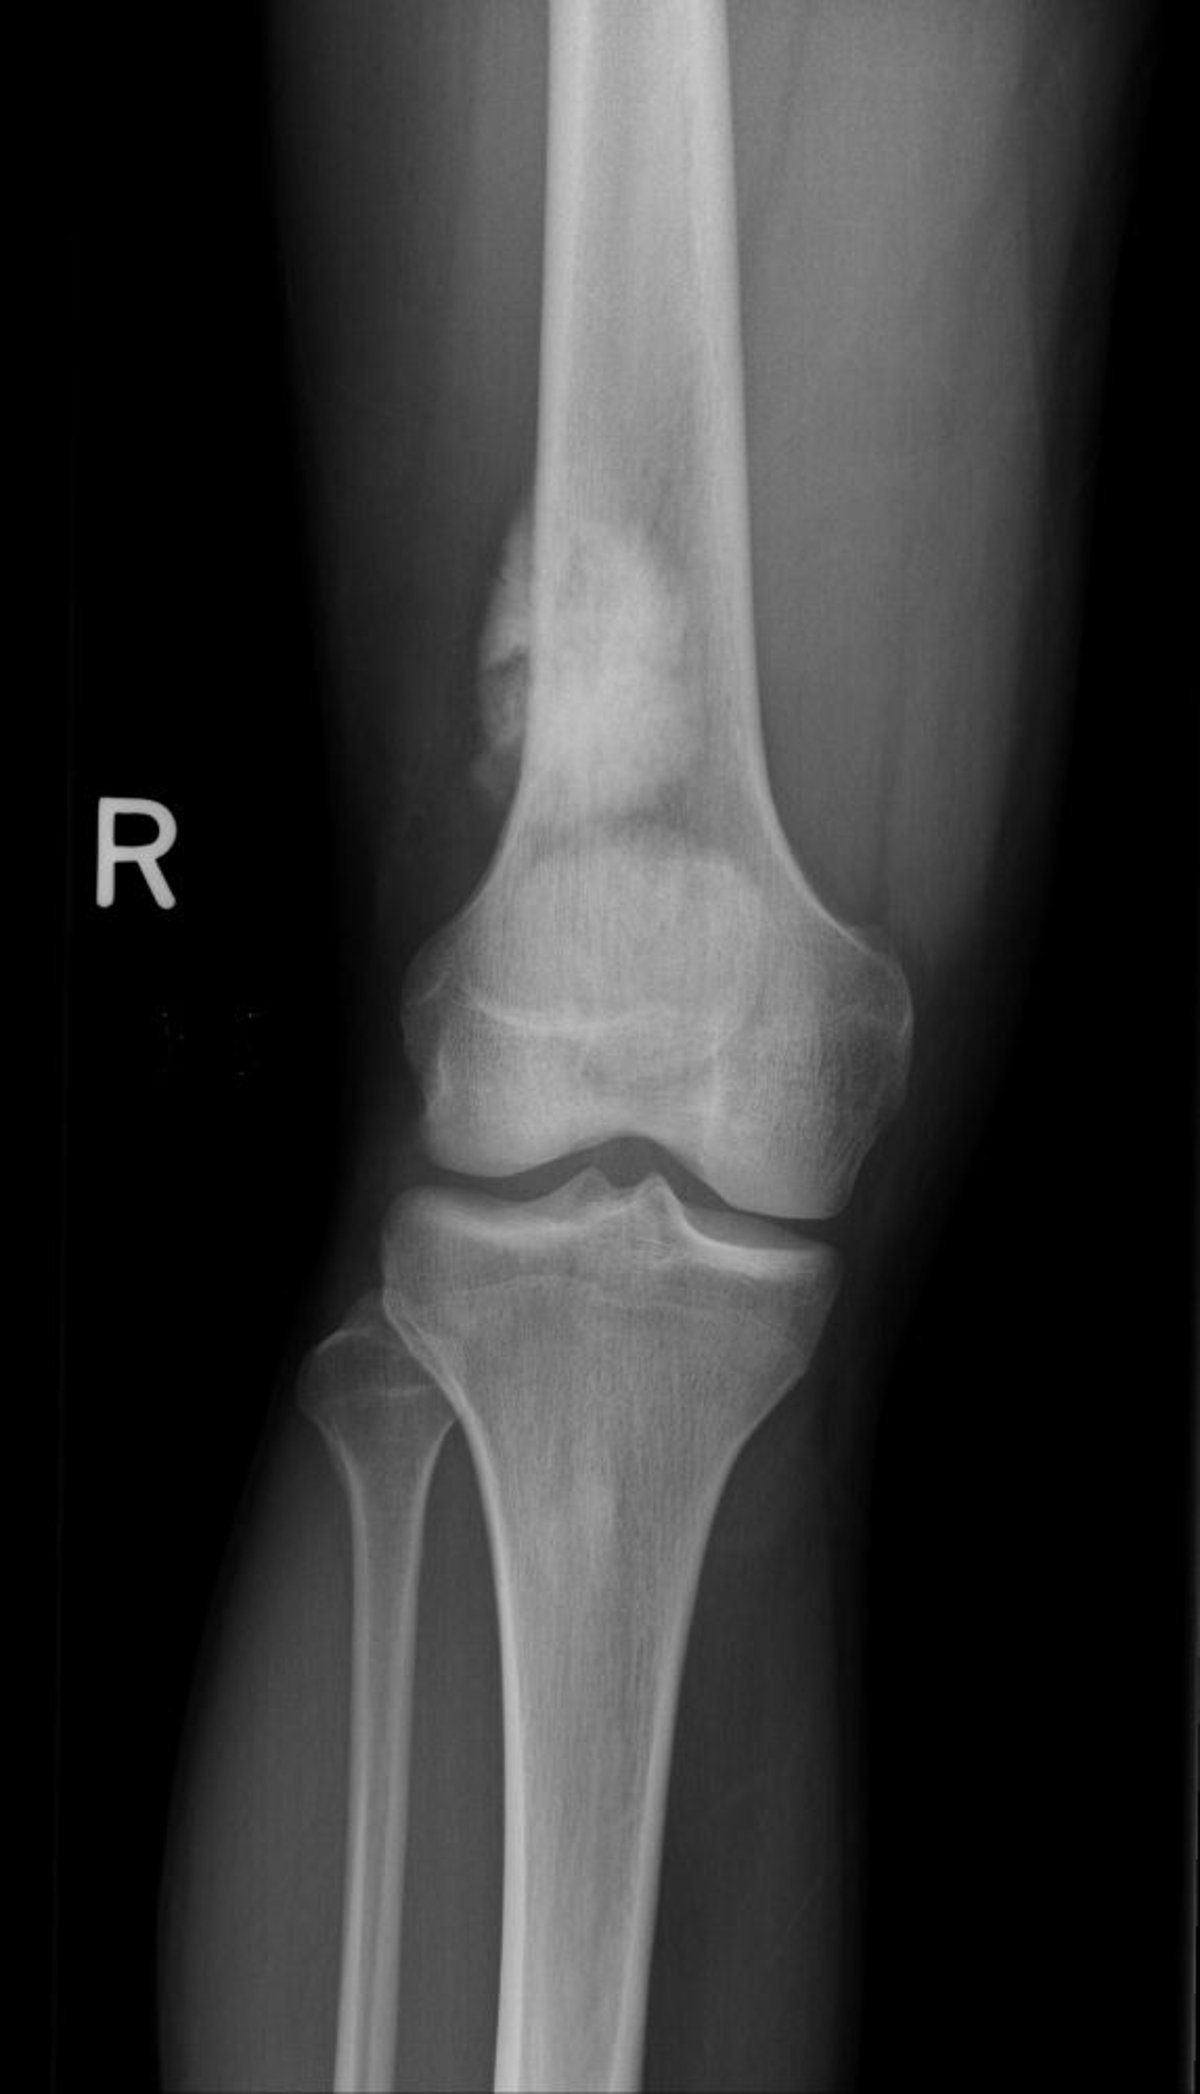

Esta radiografia do joelho mostra um osteossarcoma no osso da coxa acima do joelho.

Imagem por cortesia do Dr. Michael J. Joyce e do Dr. Hakan Ilaslan.